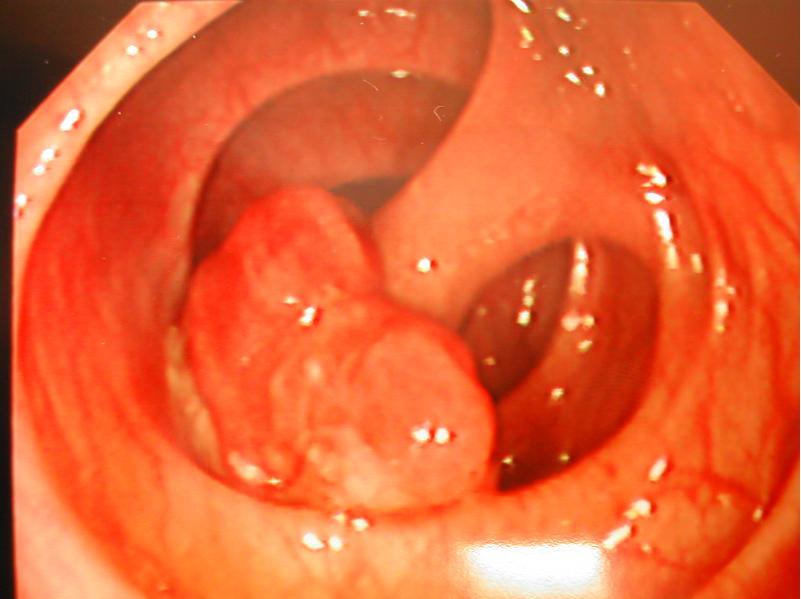

腸息肉有什么癥狀

在臨床醫(yī)學(xué)上,只有一小部分的腸息肉患者會(huì)出現(xiàn)便血和便秘以及腹痛腹瀉的癥狀,而且這些癥狀也缺乏特異性。如果患者是有癥狀的結(jié)腸腺瘤,大多都會(huì)出現(xiàn)大便帶血和粘液血便,這種情況最多見,基本上都會(huì)出現(xiàn)在比較大的直腸息肉上,有時(shí)候也有可能會(huì)大量的出血,還有一些患者因?yàn)橄⑷獬霈F(xiàn)長期的慢性失血,導(dǎo)致引起貧血。根據(jù)大多患者的情況來看,除了炎性息肉之外的大部分腸息肉并沒有任何癥狀。

如果患者直腸上的腺瘤比較大的話,還有可能會(huì)引起大便增多或者肛門帶有下墜感,甚至還會(huì)出現(xiàn)脫垂出肛門的現(xiàn)象。還有一種比較少見的情況,結(jié)腸腺瘤也有可能會(huì)出現(xiàn)腹絞痛和腸套疊。若是小腸息肉的話,患者不會(huì)有比較明顯的癥狀,但是也會(huì)表現(xiàn)出反復(fù)發(fā)作的腸道出血和腹痛現(xiàn)象。